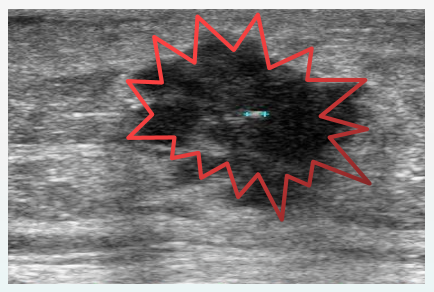

4类为可疑恶性病变,恶性的危险性 >2%,但<95%

4类又可以分为三个亚型: #4A 恶性可能>2%,但≦10% (低度) #4B 恶性可能>10%,但≦50%(中度) #4C 恶性可能>50%,但<95%(较大可能) 注:分层只是为了更好地交流

患者要经常“自摸” 如结节突然增大要尽快复查确诊